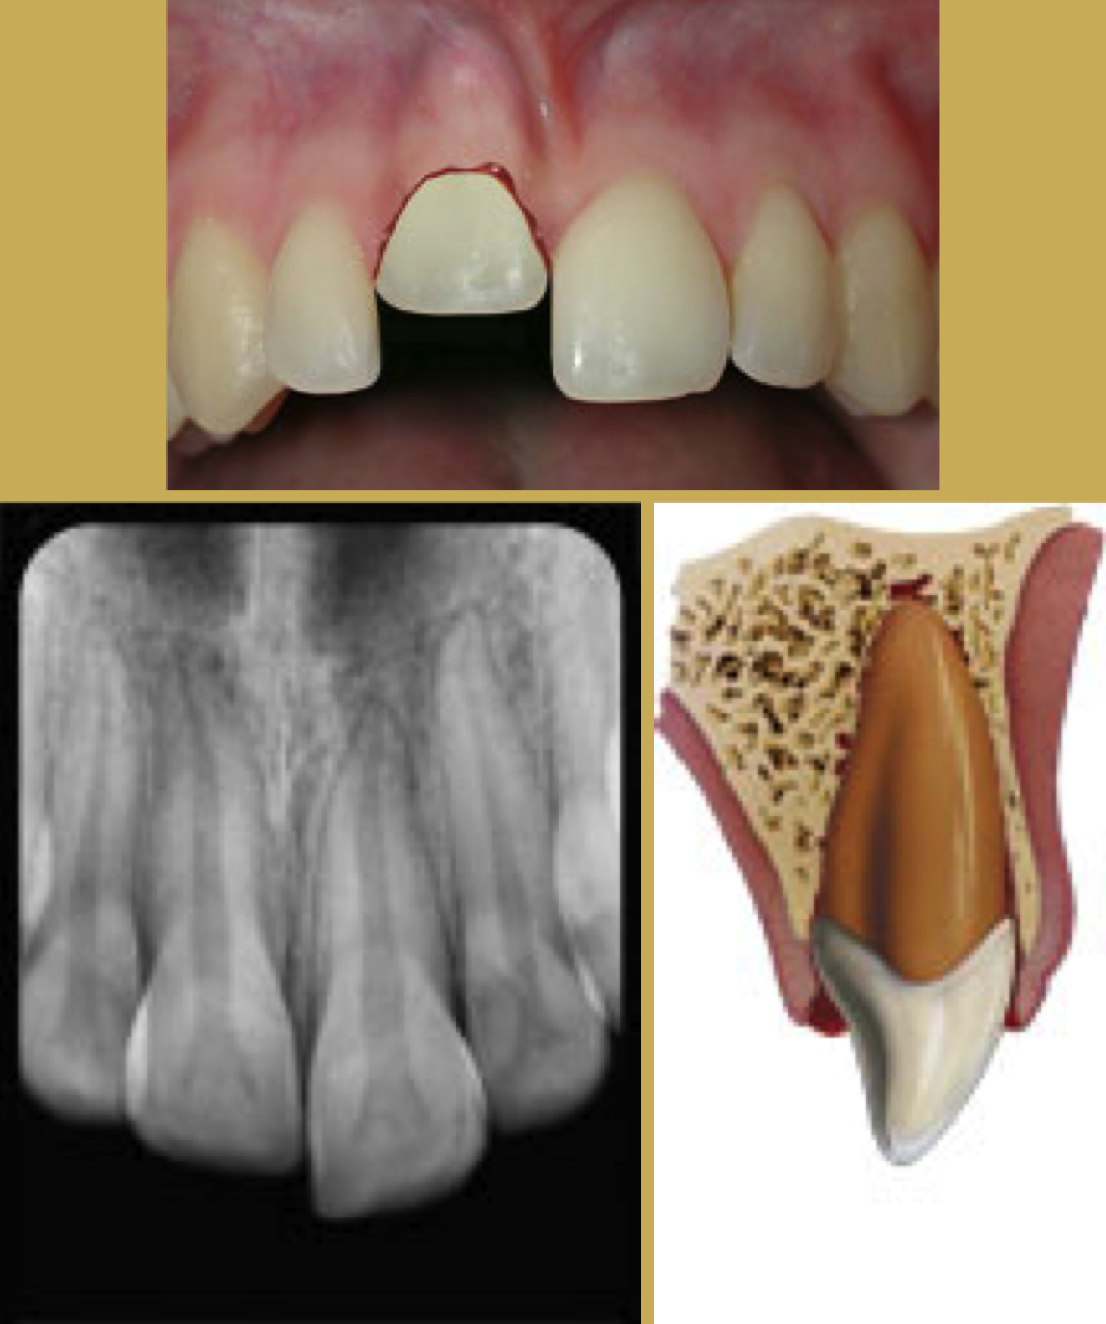

Tooth Extrusion

The tooth is displaced partially out of the socket by the trauma (Figure 4). It is usually displaced palatally. The athlete should then be asked to bite down on a sterile gauze pad to temporarily splint the tooth in preparation for transport. Immediate removal from participation and referral to a trauma-ready dentist or emergency facility.44

Radiographically the tooth appears dislocated and empty at the end of the socket. Treatment is to try to reposition gently - local anesthetic is usually not needed. Check the occlusion to be sure there is no pressure on the tooth and use a non-rigid splint for two weeks. The dentist should periodically monitor the vitality of the pulp and perform root canal therapy if needed.

Fig 4. Images of Extrusion

Figure 4